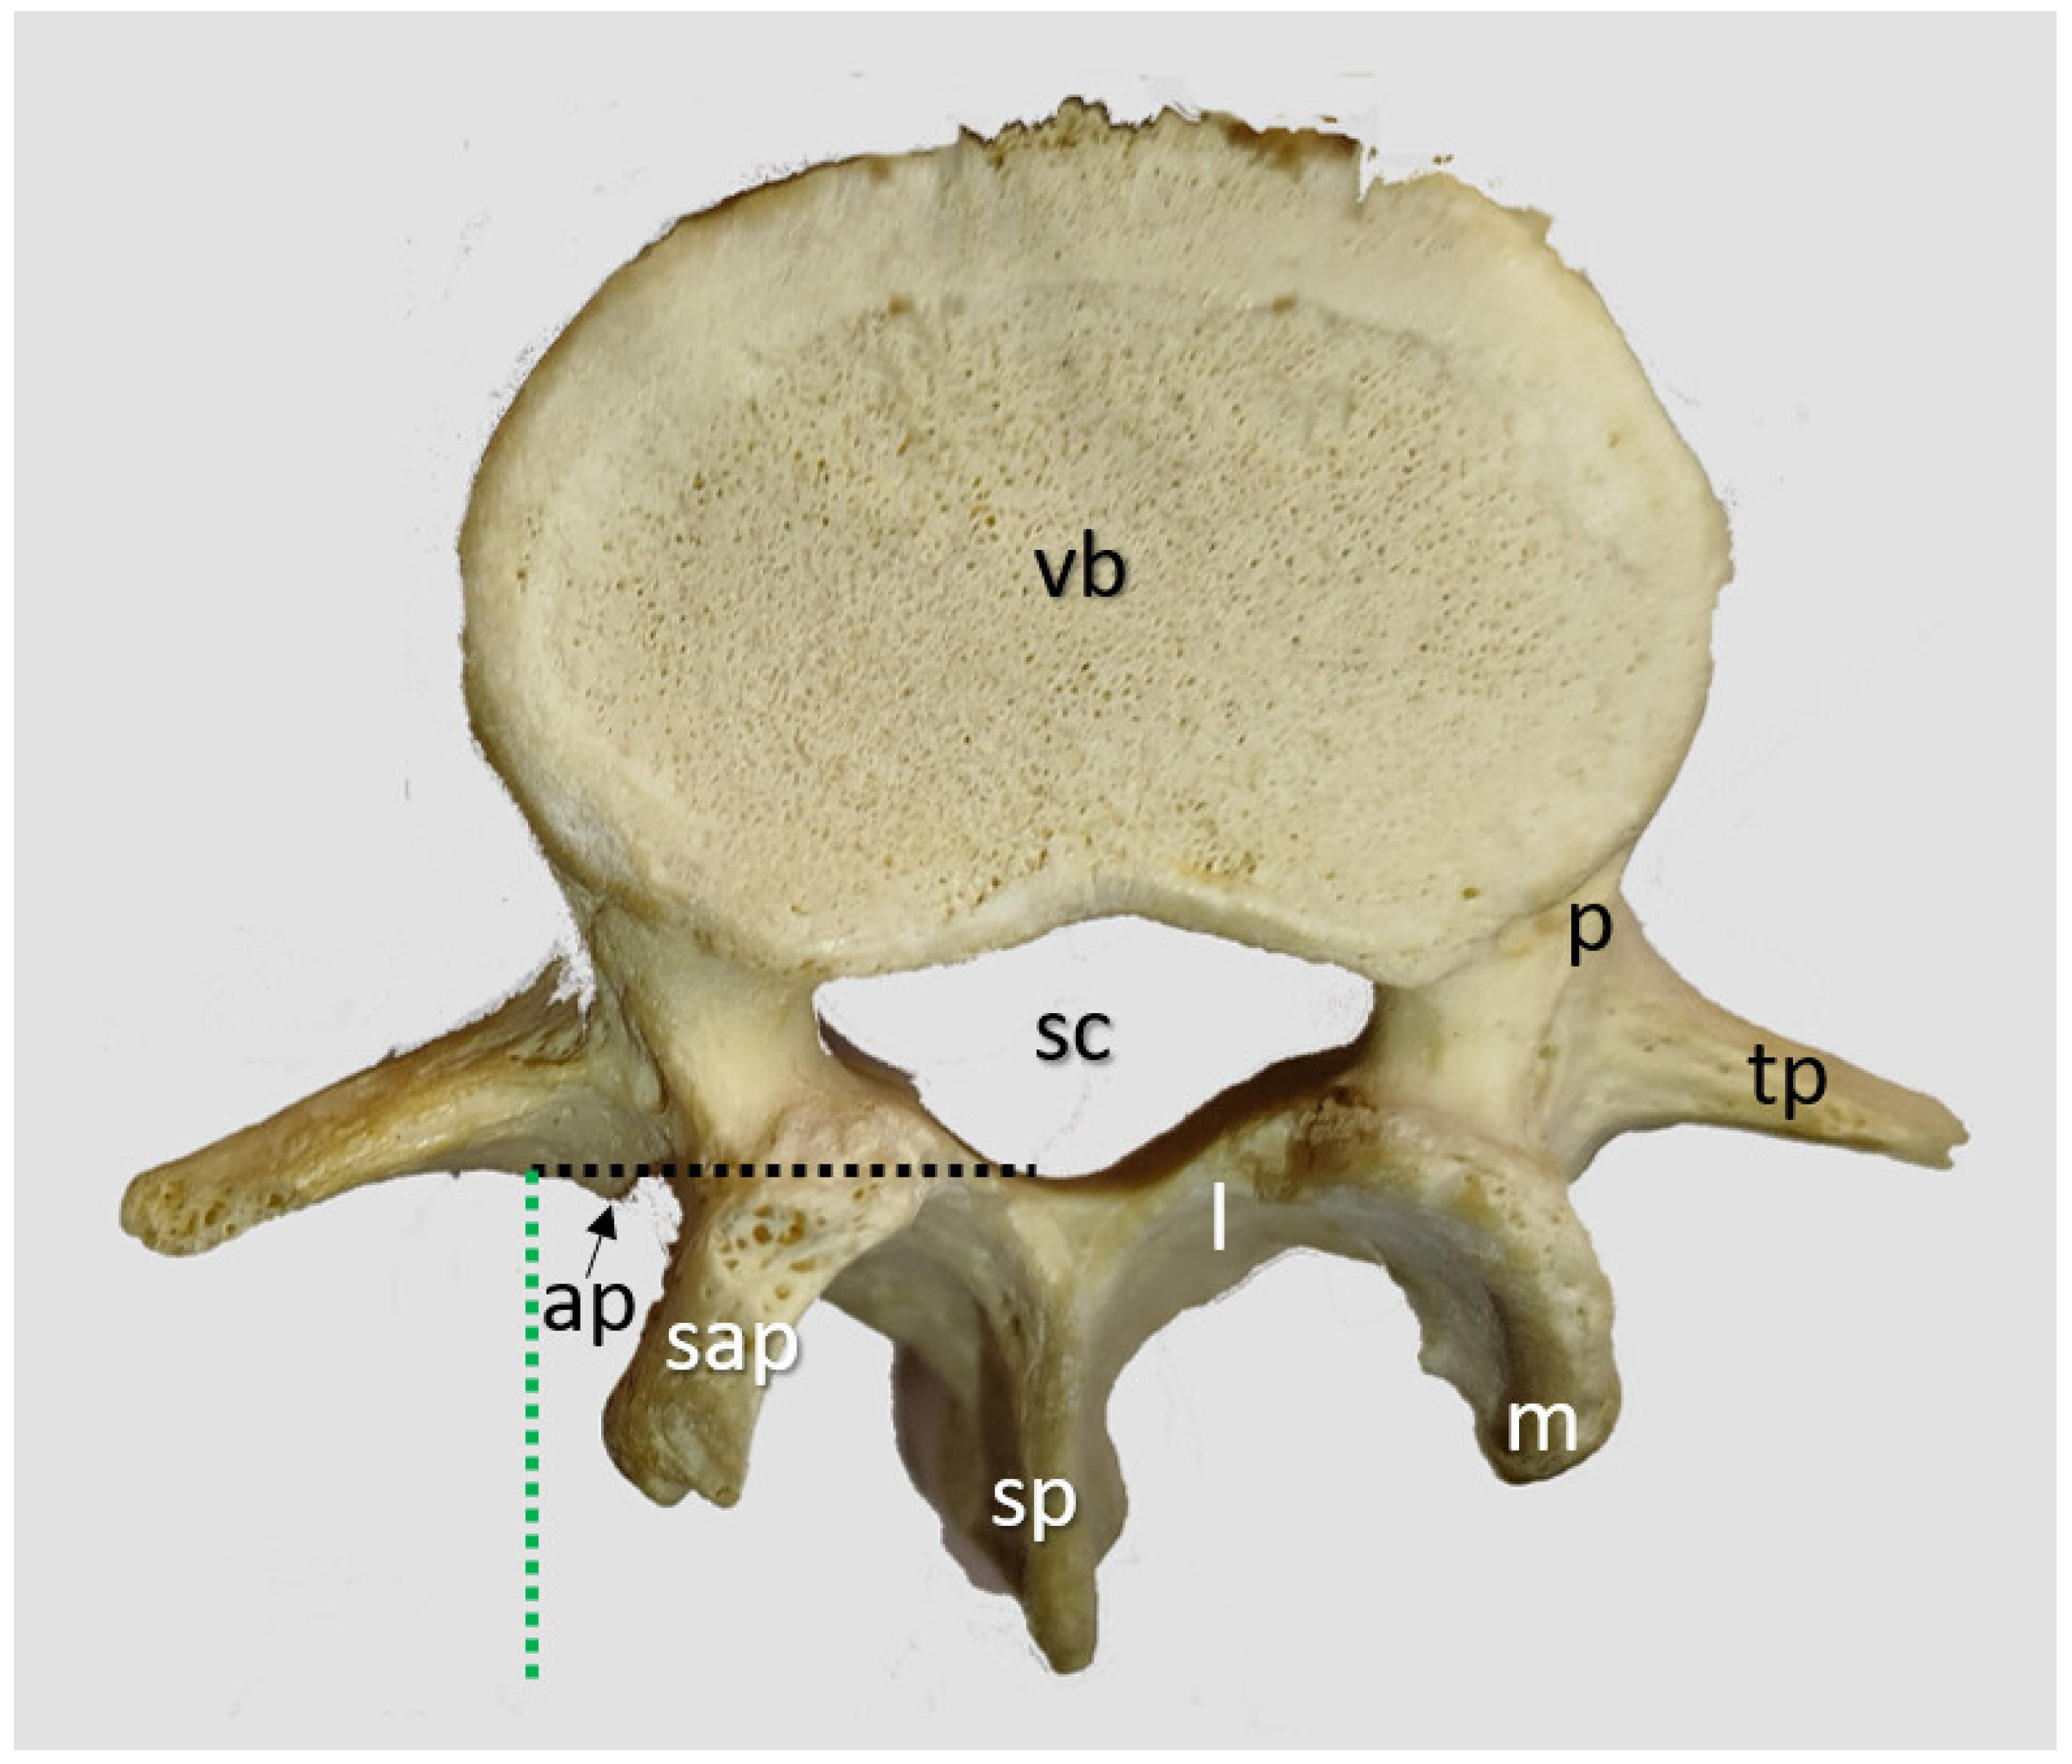

2.1.1. Transverse Process and Dural Sac Alignment

3.1. Transverse Process and Depth Level Within the Dural Sac